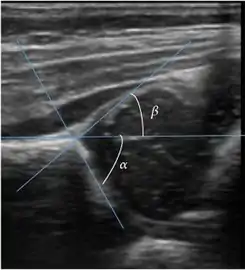

Ultrasound

Ultrasound is the first-choice technique for diagnosis of newborns hip dysplasia. In experienced hands with appropriate technology, ultrasound can also be useful during the first year of life. Some European healthcare systems encourage universal ultrasound screening in neonates between the sixth and eighth weeks. Although it shows higher initial costs caused, it leads to significant reduction in the total number and overall costs of dysplastic hips undergoing operative and nonoperative treatment.[1]

Ultrasound allows categorizing pediatric hips, according to Graf’s criteria, in four main types: normal, immature, and dysplastic (subluxed and dislocated). This classification is based on measurements of the acetabular inclination angle (alpha), cartilage roof angle (beta), and infant age. The femoral head coverage can also be determined by dividing the length of the femoral head covered by the acetabular fossa and the diameter of the femoral head. Its lower normal limits are 47% for boys and 44% for girls (Figure 11).[1]

Figure 11:

Useful ultrasound measures in neonatal hip sonography, alpha and beta angles.[1]

Measurement of femoral head coverage.[1]